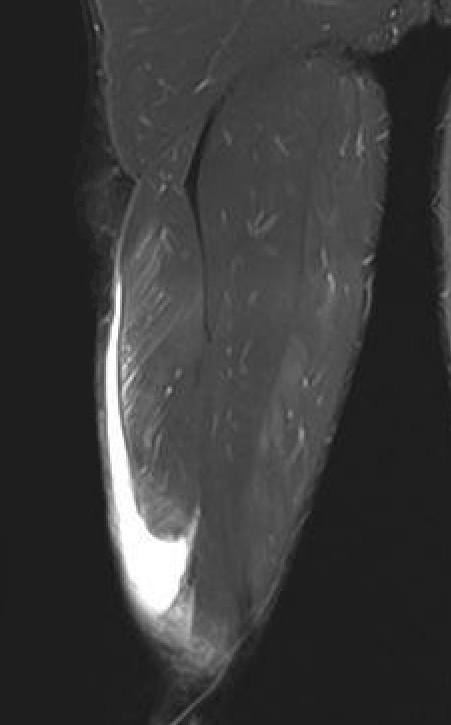

Grade 4 distal biceps femoris T Junction musculotendinous tear